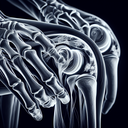

МРТ плечового суглобу

МРТ плечового суглобу – це неінвазивний метод діагностики, що дозволяє отримати детальне зображення м'яких тканин і суглобів плеча. Ця процедура особливо корисна для виявлення пошкоджень ротаторної манжети, запальних процесів, розривів зв’язок, а також інших патологій, які можуть викликати біль або обмеження рухливості. **Переваги МРТ:** - Висока чіткість зображень м’яких тканин...